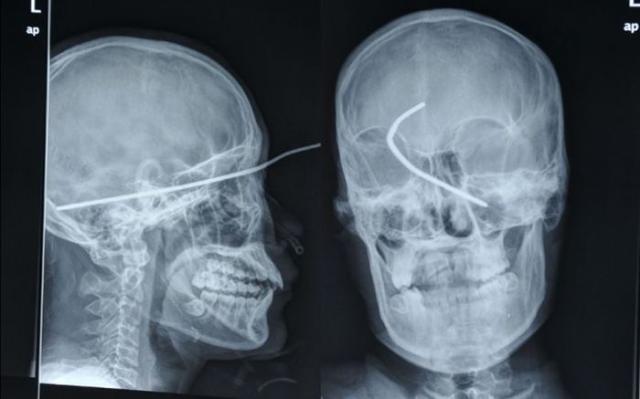

Рентгеновские снимки людей, которые умудрились сами или с чужой помощью разместить внутри своего организма разные посторонние предметы. От вилок и ножей до пуль и бензопилы (!!!). По этическим соображениям обычные снимки таких травм и повреждений выкладывать нельзя, зато рентгеновские можно – на них травмы видны достаточно условно, хоть и очень понятно.